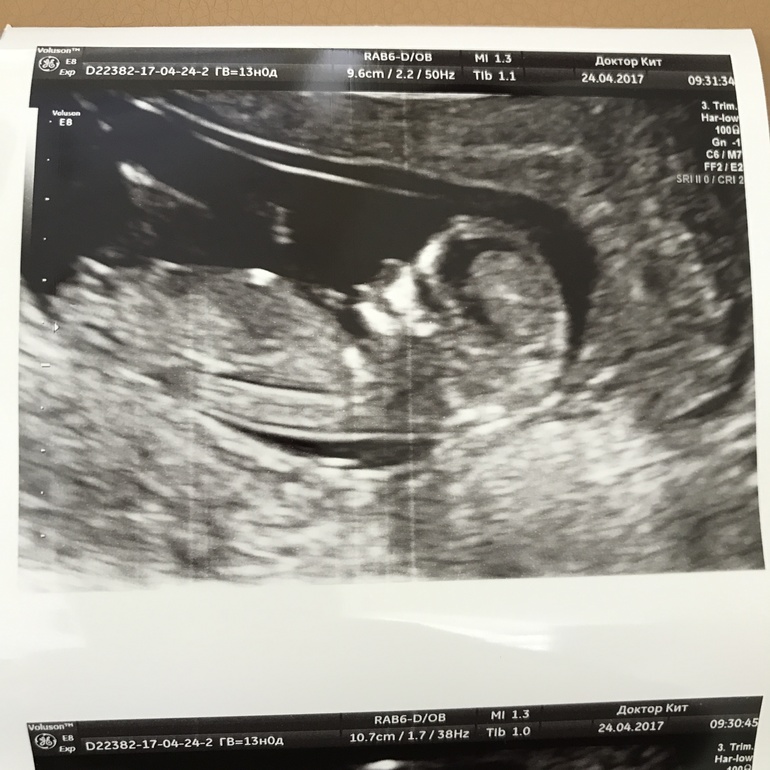

Девочки, есть ли половой бугорок на фото?

Мне тоже отпишитесь потом, кто у вас) это фото тоже 13 недель

если я правильно поняла это вот половой бугорок?)

А как по мне че то высоковато для бугорка. Прям на животике.

Мы в одно место смотрим? Там где почти ножки

это?

Пониже

Ага, ну это же уже под животиком, в конце во всяком случае